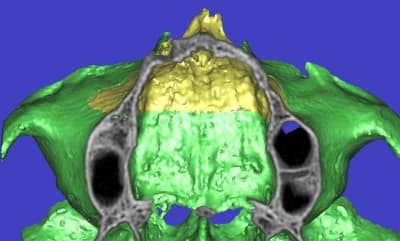

l'étude en partant des blocs standards

La première diapo est un essai pour justifier le concept (os non destiné à une utilisation greffe)

la deuxième est "tapée" dans une tête de femur de mauvais qualité (rejetée)

la troisième et suivante ce sont "les greffons" définitifs.

La précision 3D du scan est elle suffisante pour une adaptation passive sur l'os réel ?

La tu nous montres sur un stereolitique obtenu à partir du scan, ok ça colle mais en bouche ?

concept très prometteur. on obtient effectivement un contact intime du greffon avec le site receveur.